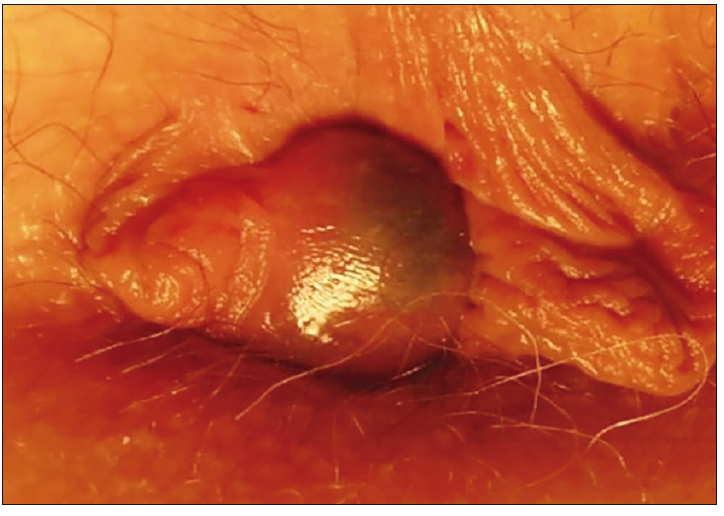

Como tumores no dolorosos podemos considerar los plicomas, condilomas y hemorroides. Los plicomas son pliegues de la piel del ano que surgen como consecuencia de alguna cicatrización o inflamación (Figura 1). En la inspección y la palpación son blandos, móviles y finos. En la mayoría de las ocasiones son asintomáticos y sólo el paciente requiere la reafirmación de que se trata de una afección benigna. Si son de gran volumen o generan problemas higiénicos se recomienda la resección quirúrgica.11

Figura 1. Plicomas anales: pliegues cutáneos de la piel anal. Son blandos, móviles,

no dolorosos y no modifican su tamaño con los esfuerzos